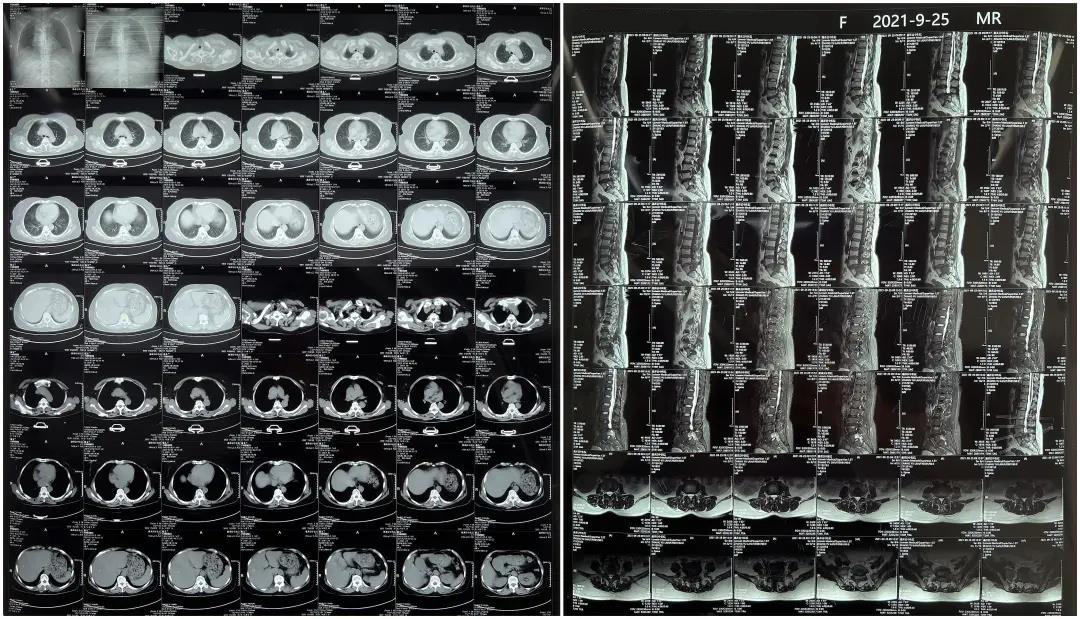

患者1:女性,56歲,L5/S1椎間盤椎板減壓+釘棒固定術

患者下腰部疼痛,活動受限,伴有左下肢疼痛5年,久站或彎腰干活時疼痛加劇,臥床休息后疼痛癥狀緩解,近一個月情況加重,需行椎板減壓+釘棒固定術。

術前患者核磁共振圖像

顯示L3/4、L4/5椎間盤突出,L5-S1水平椎管內(nèi)占位